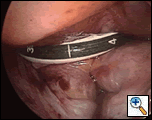

Once the tips of the two catheters are available extracorporeally to the surgeon, they are sewn together with a simple stitch of 2-0 or 3-0 silk. Traction is then placed on the flared ends of the catheters from the right side of the chest and the whole assembly is seen to come to rest posterior to the left atrial appendage and around the pulmonary veins. It is very important to observe this step directly (Figure 7), as malposition usually results in a guidance system wrongly located anterior to the LA appendage with resultant ablation of the circumflex coronary artery.

The Flex 10 MWA probe is then sutured to the flared end of the transverse sinus catheter. Traction is placed on the oblique sinus catheter and the Flex 10 is introduced into the right chest while observing its progress from the camera still positioned in the left pleural space. It is important to thread the Flex 10 into the right chest with the flat surface of the probe (the antenna side) facing inferiorly, so that the antenna will come to rest against the dome of the left atrium through the transverse sinus. If the probe is seen to be coming around the left pulmonary veins in an incorrect orientation, the handle of the device may be rotated and the threading process proceeds and usually this will correct the problem. Always confirm that the Flex 10 remains posterior to the LA appendage as it is threaded (Figure 8).